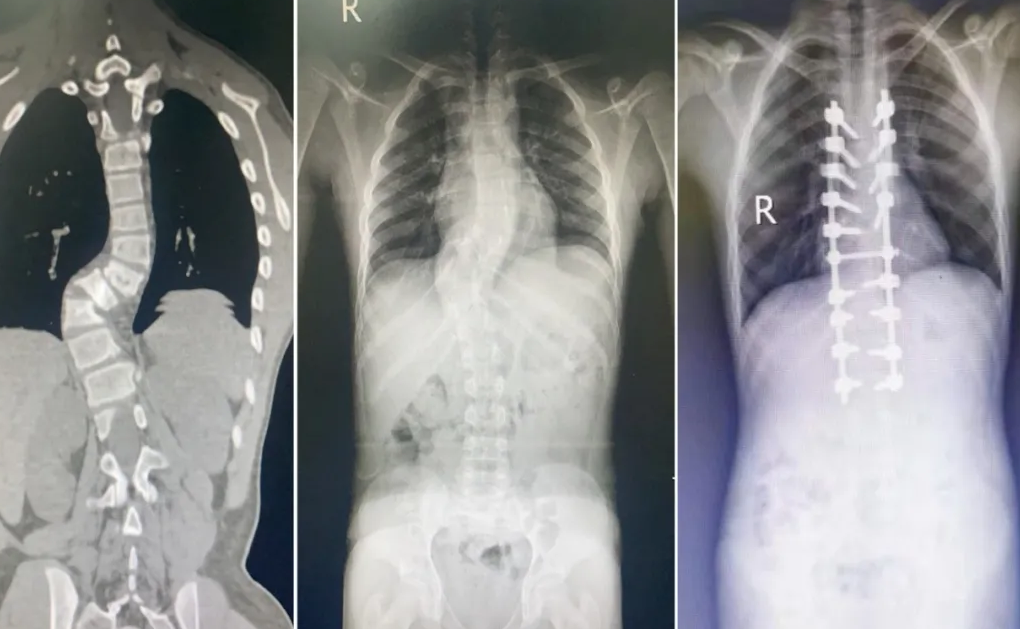

入院后,脊柱骨科艾孜孜江医生负责阿布都的诊疗事宜。他通过详细询问病史,仔细进行查体,并完善相关检查后发现:阿布都的主弯胸椎侧弯 cobb 角度接近 60°,脊柱序列不连续,其中胸 9-10 椎体和小关节已经严重脱位,多个椎体、椎板发育不良,椎板薄如纸,同时合并硬脊膜膨出,脊髓开始受到压迫。

在脊柱骨科医护人员的精心护理下,阿布都一天天好转,术后第 3 天即可下地行走,身高增加了 5 cm!下地的当天,阿布都开心、激动地告诉喀什地区第一人民医院医护人员,「我比妈妈高了!」术后复查显示,阿布都的胸弯 Cobb 角已经减小到了 20°,矫正度达 70%,脊柱序列和平衡均恢复满意,小小侧弯少年重新挺直腰杆,迎接灿烂人生!